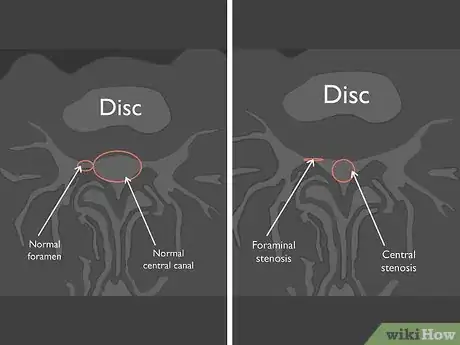

5Look at the space available for your nerves. Axial MRIs allow you to see more detail of the nerve canal and nerves traveling down to your legs. If you have a protruding or herniated disc, your nerves may not have enough space. When this happens, your doctor will say that the nerve is "impinged." The nerves at each level of your lumbar spine travel to a different part of your legs. If you have an impinged nerve, you may have pain, weakness, or numbness in the corresponding part of your body:[14]

6Check for signs of disks pressing into the spinal canal. Sometimes wear and tear on the lumbar vertebrae can cause spinal disks to bulge into the spinal canal. This condition, called spinal stenosis, causes a narrowing of the space inside your spinal column, which can put pressure on the nerves in your spinal cord.[15] Look for narrow areas in the dural sac, or the tube that surrounds your spinal cord.

- To meet the criteria for spinal stenosis, a sagittal MRI should show a dural sac diameter of less than 10 mm at the point of compression.[16]

- Spinal stenosis is different from foraminal stenosis, which is a narrowing of the holes in the vertebrae that the spinal nerves exit through.